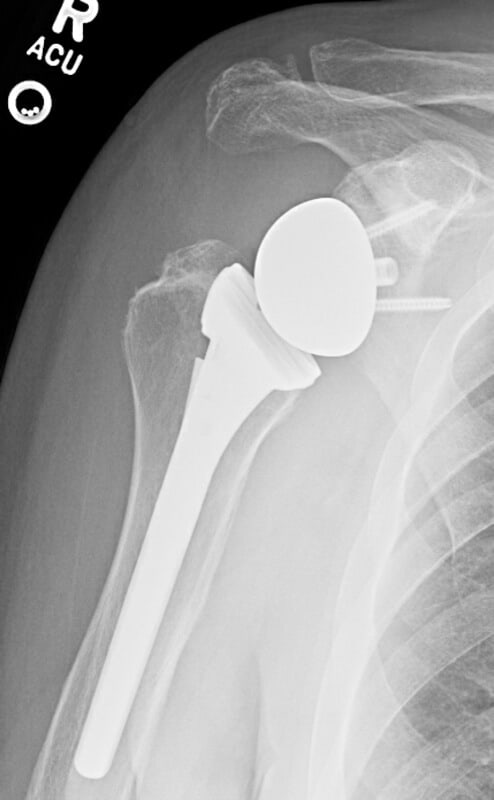

DePuy, DeltaXtend